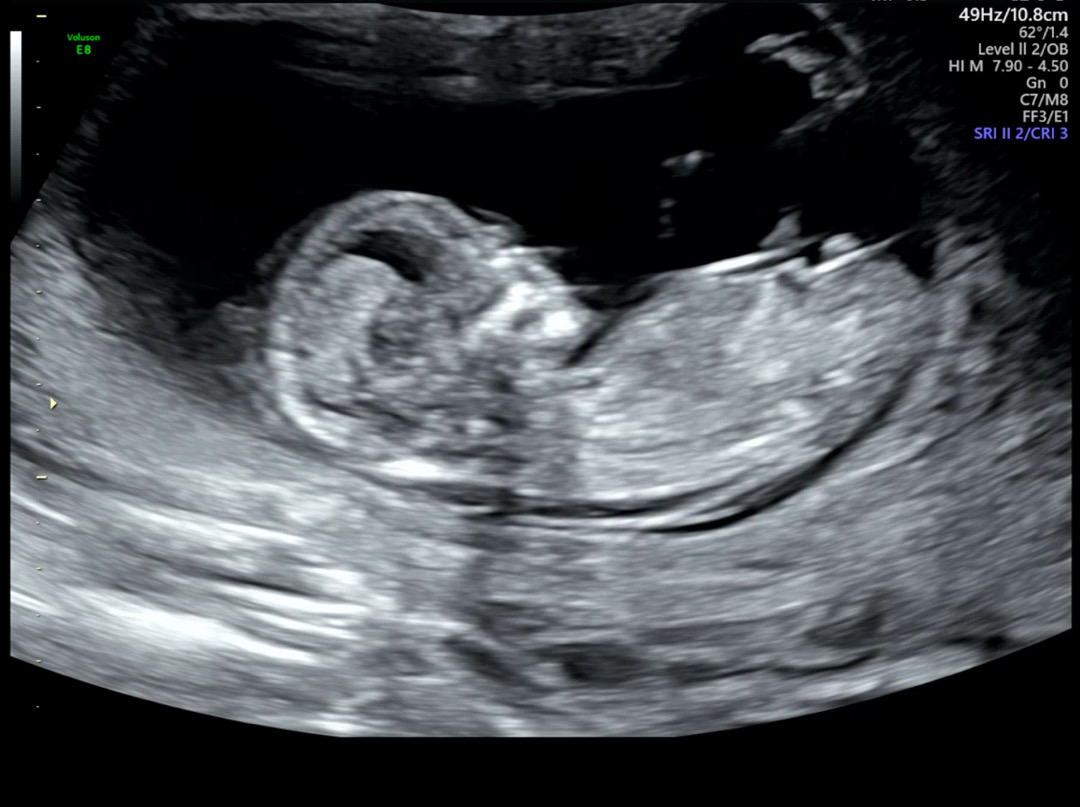

12주 6일차 각도법 봐주세용😆

12주 6일차 각도법 봐주세요오! ㅎㅎ 딸인가요 아들인가요?!